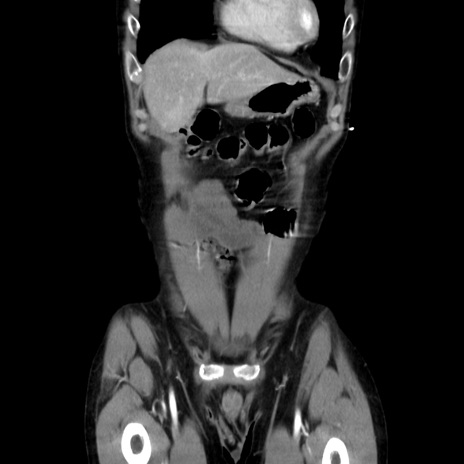

症例37(冠状断像)

【症例】40歳代 男性

【主訴】腹痛

【現病歴】4時間ほど前に電車に乗車中に臍部上より腹痛出現。徐々に増悪し起立困難となり、救急外来受診。生ものは数日食べていない。今朝お雑煮を食べた。

【身体所見】BT 36.8℃、BP 117/84mmHg、HR 91/min、SpO2 97%、苦悶様、腹部:臍上部広範囲圧痛あり、反跳痛±

【データ】WBC 8100、CRP 0.03